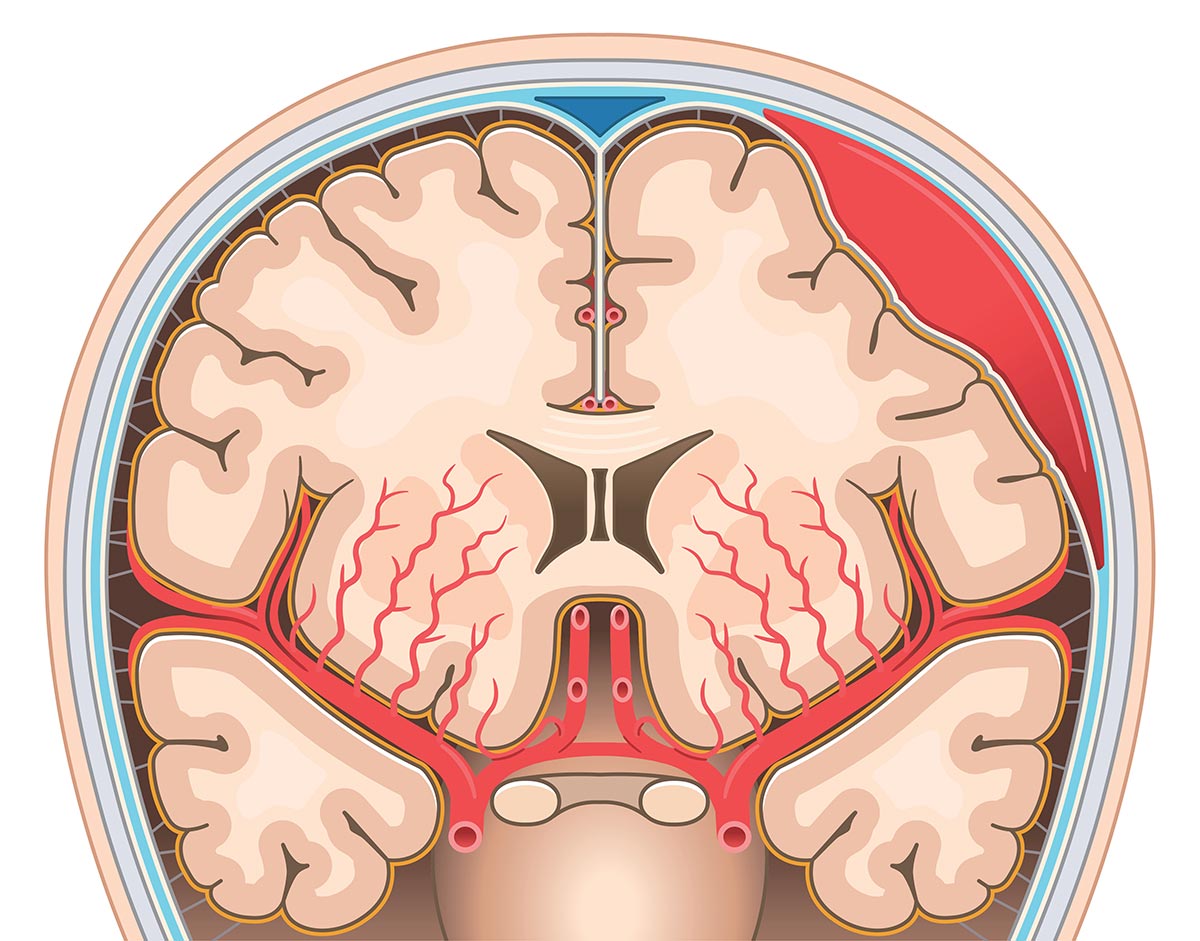

- Intrakranielle Hämatome – chronisches Subduralhämatom

Intrakranielle Hämatome entstehen durch Blutungen innerhalb des Schädels, häufig infolge eines Traumas. Eine besondere Form stellt das Subduralhämatom dar, bei dem sich Blut zwischen harter Hirnhaut und Gehirn ansammelt. Akute Subduralhämatome können rasch lebensbedrohlich sein, während chronische Subduralhämatome sich oft schleichend entwickeln und insbesondere bei älteren Patientinnen und Patienten auftreten. Typische Symptome sind Kopfschmerzen, Sprachstörungen, Bewusstseinsveränderungen sowie neurologische Ausfälle wie diskret beginnende und zunehmende Halbseitenlähmungen oder eine zunehmende Gangunsicherheit. Die Diagnostik erfolgt bildgebend, die Therapie richtet sich nach Ausdehnung, Symptomatik und klinischem Verlauf. In vielen Fällen ist eine operative Entlastung erforderlich.